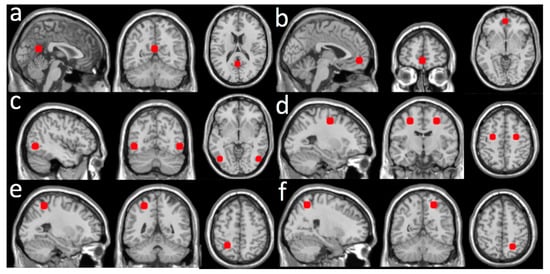

Due to the minimal contamination from motion artifacts and physiological noises, the dASL image time series were not processed for removing the noises. Global CBF values, averaged over the whole brain, were regressed out from the dASL image time series. Eight seeds were chosen from the default mode network (DMN) and dorsal attention network (DAN). Two seeds were from DMN: the posterior cingulate cortex (PCC) and the ventromedial prefrontal cortex (vmPFC). Six seeds were from DAN: the left middle temporal area (LMT), the right middle temporal area (RMT), the left frontal eye field (LFE), the right frontal eye field (RFE), the left superior parietal lobule (LSPL), and the right superior parietal lobule (RSPL). The seeds were chosen to cover different anatomical extents: frontal cortex, parietal cortex, and temporal cortex. All seed regions of interest (ROIs) were defined as a sphere with a volume of ~2 cm3. The centers of the seed ROIs were selected from a previous study [] (see a summary in Figure 1) that examined the spatial distribution of DMN and DAN. For each subject, a CBF rsFC map with a seed ROI was calculated as voxel-wise Pearson correlation coefficients between the dASL time series and the time series of each seed ROI. All Individual CBF rsFC maps with all seed ROIs were transformed into z score maps by using a Fisher z transformation to improve normality for group-level comparisons.

Figure 1.

ROIs constructed from the seeds with the MNI coordinates listed: (a) posterior cingulate cortex (PCC, (1, −55, 17) mm); (b) ventromedial prefrontal cortex (PFC, (0, 51, −7) mm); (c) left and right middle temporal area (LMT, (−45, −69, −2) mm and RMT, (50, −69, −3) mm); (d) left and right frontal eye fields (LFE, (−25, −8, 50) mm and RFE, (27, −8, 50) mm); (e) left superior parietal lobule (LSPL, (−27, −52, 57) mm); (f) right superior parietal lobule (RSPL, (24, −56, 55) mm).